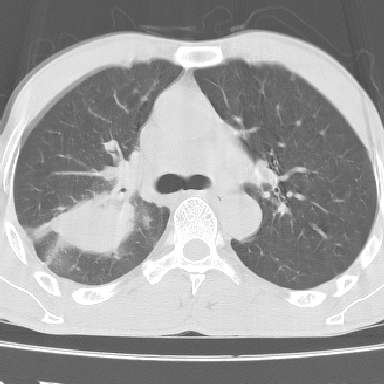

以下是引用lpc0ct在2006-11-28 16:12:00的发言:[br]大家图文并貌分析的太全面了,没有可说的,同意 [br] 右肺上叶中心型肺癌伴肺门、纵隔淋巴结转移.[br]

以下是引用dyqct在2006-11-28 16:00:00的发言:[br]右肺上叶中心型肺癌伴肺门、纵隔淋巴结转移。[br][br]